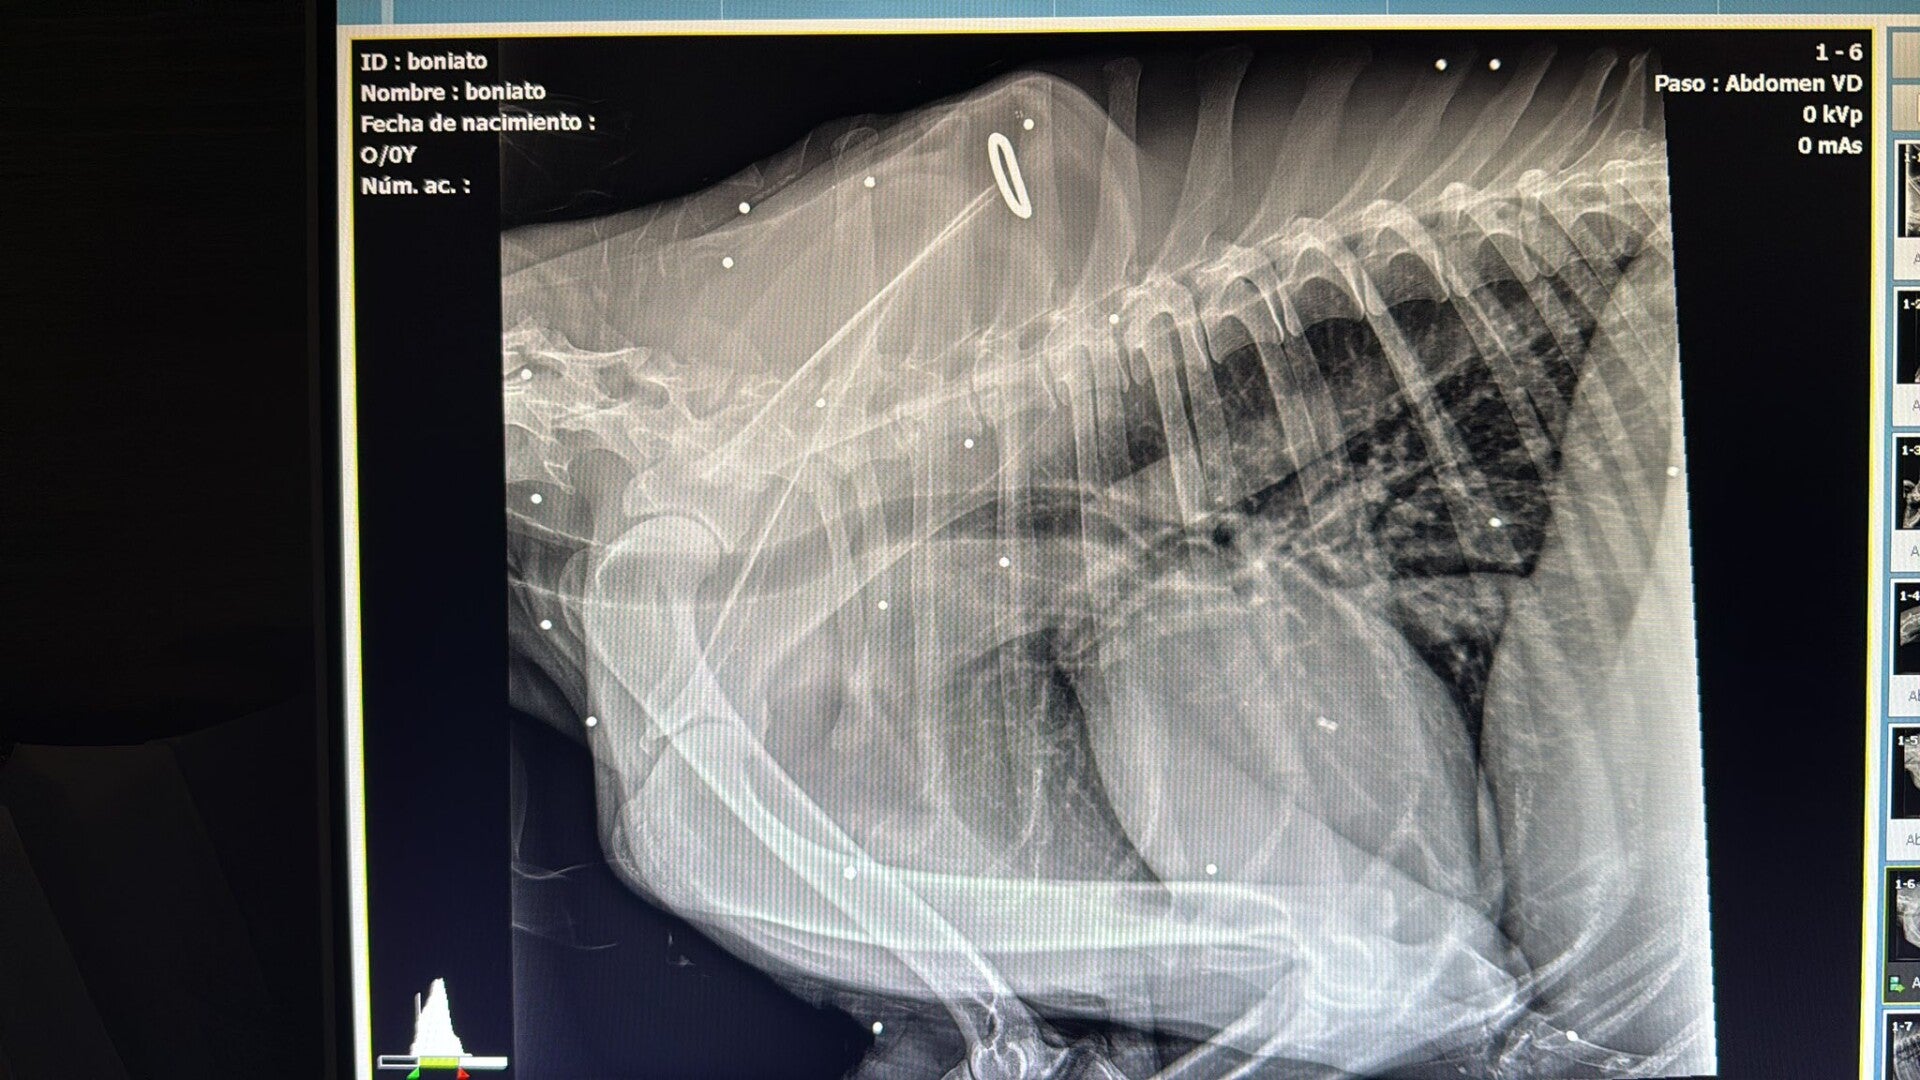

Dit zijn de röntgenfoto’s van het kleine lijfje van Boniato. Elk wit puntje dat je ziet is een stukje lood. Ze zijn zelfs gestopt met tellen hoeveel het er zijn. Er zit lood in bijna elk deel van zijn lichaam, zelfs bij zijn hart, longen en langs zijn wervelkolom. Iemand heeft simpelweg geprobeerd hem te doden door herhaaldelijk op hem te schieten — een triest en herkenbaar stempel van een jager. Geen woorden voor…